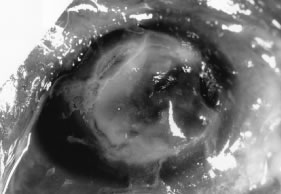

In the early stages of infection, filamentous fungi produce signs that are readily distinguishable from yeast or bacterial keratitis. The most distinctive sign is the presence of delicate, fine, feathery, opalescent, gray-white or yellow-white material in the anterior stroma, surrounded by scant cellular infiltrate or edema (Fig. 1). The epithelium may be intact. The overlying epithelium may be granular and the surface elevated and irregular in contour. Linear infiltrates typically extend into the adjacent stroma. Multiple discrete opacities may develop outside the perimeter of the principal focus of inflammation, either separated by clear stroma or linked by fine linear collections of inflammatory cells and material (Figs. 2 and 3). In the absence of inflammation in the adjacent stroma, branching hyphal fragments may be visualized by biomicroscopy (Figs. 4 and 5). Confocal microscopy may also detect hyphal elements within the stroma.28,29 Peripheral infection resembles noninfectious marginal infiltrative and ulcerative keratitis (Fig. 6). Multifocal keratitis may develop after contact lens wear or injury by multiple projectiles (Fig. 7). In the early stages, iritis is present and the intraocular pressure remains normal. Inappropriate, empirical therapy of fungal keratitis with topical fluoroquinolone or aminoglycoside antibiotics may suppress or eliminate the superficial elements but allow extension of the organisms into the stroma because these agents may possess selective antifungal activity.4,30,31

There is no distinguishing clinical sign by which to recognize the genus or species of the infectious filamentous fungus. F. solani is the most virulent organism and typically produces rapidly progressive infection characterized by epithelial and stromal ulceration, dense stromal necrosis, abundant cellular infiltrate, and edema in the adjacent stroma and hypopyon (Figs. 8 and 9). Delicate feathery components are transient. Individual hyphal fragments are rarely visualized. Infection by certain species of Aspergillus and Scedosporium (Figs. 10 and 11) resembles F. solani keratitis and progresses rapidly. Infection by less virulent organisms, such as Curvularia and Alternaria species, produces small, focal (less than 3-mm diameter) areas of nonnecrotizing stromal inflammation with delicate feathery borders (see Fig. 1 and Fig. 12). Macroscopic pigmentation may develop in keratitis caused by Alternaria, Curvularia, and other dematiaceous fungi (Fig. 13).4,11,14 The central component may progress to dense, opaque, gray-white suppuration in the deep stroma without enlargement in total area and may be accompanied by mild inflammation in the adjacent stroma. Iritis is minimal to moderate. Infection caused by other, relatively less virulent organisms resembles herpes simplex or noninfectious keratitis (Fig. 14).

Advanced, severe filamentous fungal or yeast keratitis is indistinguishable from keratitis caused by virulent bacteria such as Staphylococcus aureus or Pseudomonas aeruginosa. The area of epithelial and stromal ulceration is large. Dense, opaque, homogenous, yellow-white stromal necrosis develop and is surrounded by confluent cellular infiltrate and full-thickness stromal edema (Figs. 19, 20, 21). Hyphal elements may penetrate Descemet's membrane and endothelium and be visualized in the anterior chamber. Fibrinous material accumulates over the endothelium, anterior chamber angle, and iris. Pain is typically severe. Secondary ocular hypertension may ensue. Progressive stromal necrosis leads to corneal perforation and, rarely, consecutive endophthalmitis.